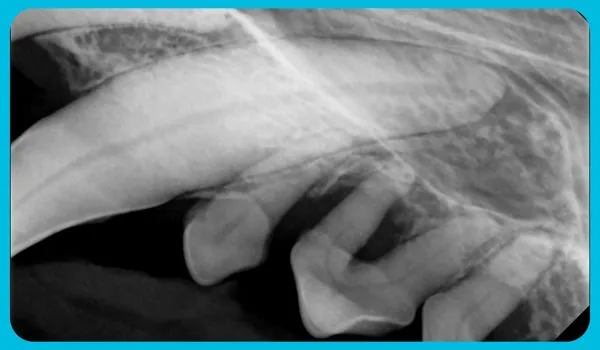

He was placed in foster care while awaiting surgery, where he received patience and comfort as his treatment plan was developed. On November 13, Harley was admitted to our on-site Companion Animal Hospital for his first dental procedure. As part of our advanced protocol, full-mouth dental radiographs were taken—because what lies beneath the gums can’t always be seen. The images revealed extensive disease, requiring a careful, multi-stage approach.

Supported with IV fluids and closely monitored, Harley underwent his first procedure, during which 14 teeth were extracted. He returned to foster care to recover and regain strength before the next stage of surgery.

On December 7, Harley returned for his second procedure. This time, 20 more teeth were carefully removed and sutured, leaving him with just eight remaining teeth. Thanks to the skill and dedication of our veterinary team—including Dr. Dam and our Registered Veterinary Technicians—Harley’s recovery was managed with exceptional expertise and compassion.